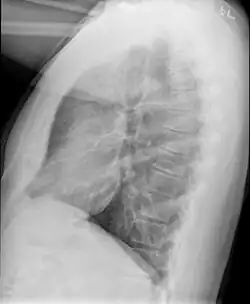

Medical imaging

Early in the disease chest radiography is typically normal but may show hyperinflation.[6] As the disease progresses a reticular pattern with thickening of airway walls may be present.[4][6] HRCT can also show air trapping when the person being scanned breathes out completely; it can also show thickening in the airway and haziness in the lungs.[11] A common finding on HRCT is patchy areas of decreased lung density, signifying reduced vascular caliber and air trapping. This pattern is often described as a "mosaic pattern", and may indicate bronchiolitis obliterans.[6]